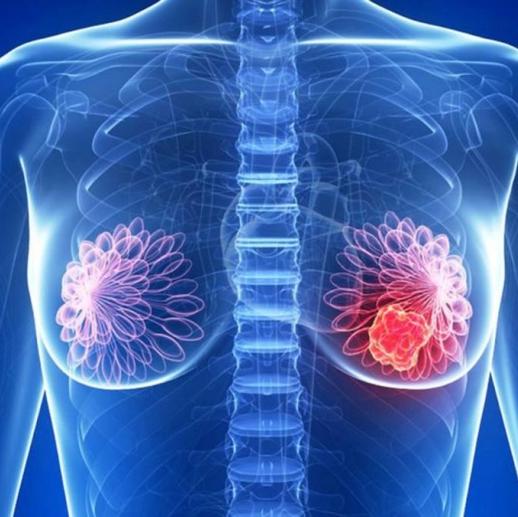

Certificado por el Consejo Mexicano de Oncología UNAM 8567091 UADY 4530325 UADY 5941906

- Diagnóstico y tratamiento avanzado de todo tipo de cáncer.

- Cirugía conservadora en cáncer de mama. - Cirugía hepatopancreatobiliar.

- Cirugía en cáncer por mínima invasión. - Ablación de tumores

Prevención, diagnóstico, tratamiento y paliación del cáncer.